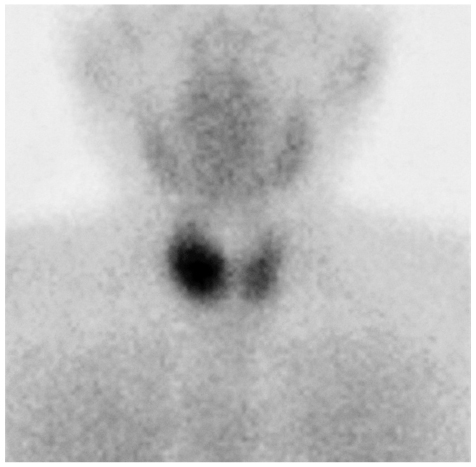

頸部超音波検査で、甲状腺右葉下極に近接して長径 3 cm の腫瘤を検出した。

99mTc-MIBI 副甲状腺シンチグラムを別に示す。